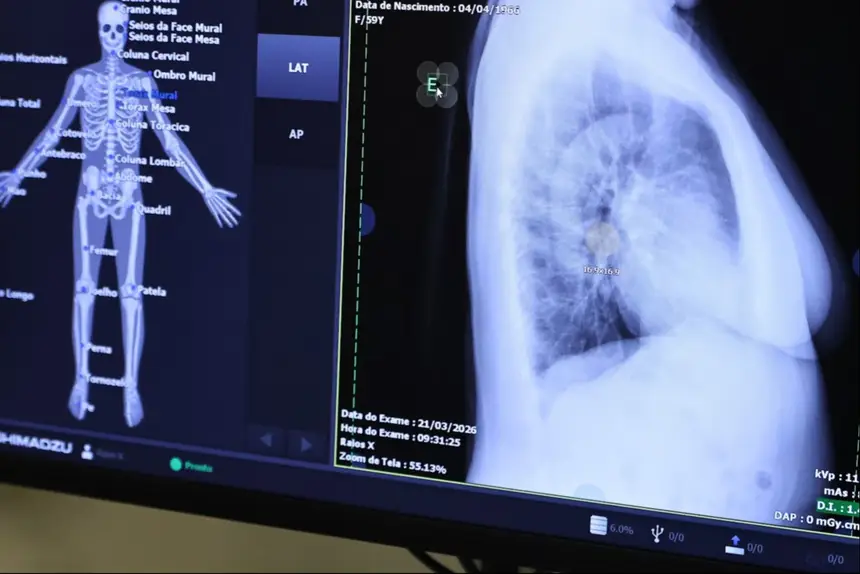

O Centro Tecnológico é composto por aparelhos de ressonância magnética, tomógrafo computadorizado, equipamento de mamografia, raio X telecomandado e densitometria óssea.

Os equipamentos foram adquiridos por meio de contratação e fazem parte do plano de qualificação de exames por imagem.